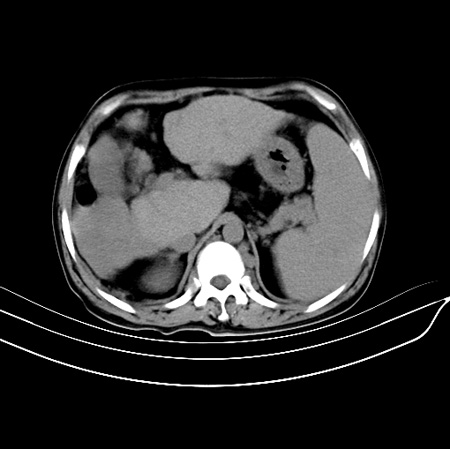

以下是引用江尾海头在2007-9-7 19:01:00的发言:[br]肝叶比例失调,肝边缘高低不平,尾状叶增大,肝裂增宽。肝右叶见较大密度减低影,边缘欠清。脾脏明显增大,胃底及奇静脉半奇静脉曲张。胆囊未见明显显示。 考虑:1、肝癌。2、肝硬化伴脾大静脉曲张。

以下是引用zhangxu5888在2007-9-7 22:31:00的发言:[br]1、肝硬化,食管 胃底及奇静脉半奇静脉曲张;2、脾脏肿大; 3、肝右叶的病灶呈锲性改变,内可见条片状钙化,边界清晰,密度明显低于周围正常肝组织,我觉得肝癌可能性不是很大, 同意楼上观点,有可能是栓塞,建议增强.